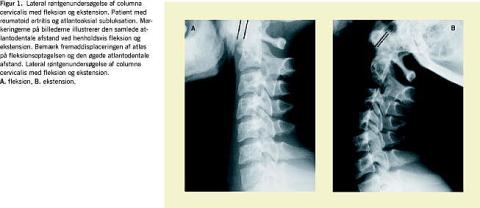

Hyppigst ses anterior atlantoaksial subluksation (aAAS), som er beskrevet i litteraturen med en incidens på 20-80% og en prævalens på 17-86%, afhængigt af patientselektion, røntgenteknik og -diagnostik [1, 3-6]. Allerede inden for de første sygdomsår er risikoen for aAAS stor [1, 4, 7-10]. Diagnosen stilles ved en lateral røntgenundersøgelse af columna cervicalis med fleksion og ekstension (Figur 1 ). På fleksionsbilledet udmåles afstanden mellem forreste atlasbue og dens axis (den atlantodentale afstand), som er patologisk ved en afstand > 3 mm [4-6, 11]. Mindre hyppige former er lateral, posterior og vertikal atlantoaksial subluksation [5, 12].